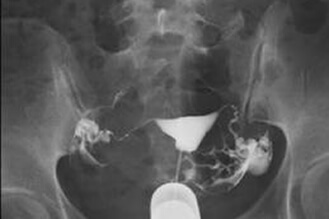

Normal salpingography,bilateral patent fallopian tubes

After a vaginal speculum is inserted to spread and hold open your vaginal walls, a syringe held at your cervical region will be used to inject a contrast medium into your uterus. If both of the fallopian tubes are patent, the contrast medium will flow from the uterus to bilateral fallopian tubes and further into the pelvic cavity. With the use of fluoroscopy, we may capture whether the contrast medium flows into the pelvic cavity. The entire examination will take approximately 10 minutes.